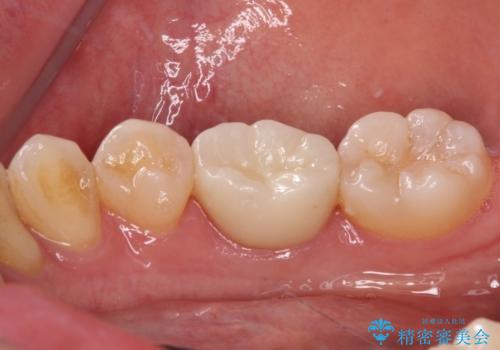

速やかに処置を進めたことで症状は落ち着き、治療後しばらくの状態では神経を取り除く可能性は低くなりました。